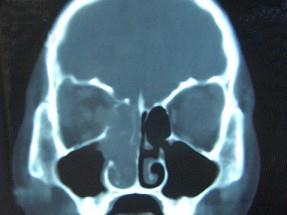

女,16岁,鼻塞、流涕一年余,失去嗅觉,影像检查如图所示,最可能的诊断是 ( )

答案: E